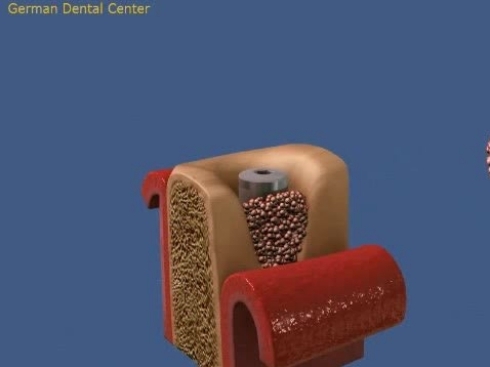

- Имплантация